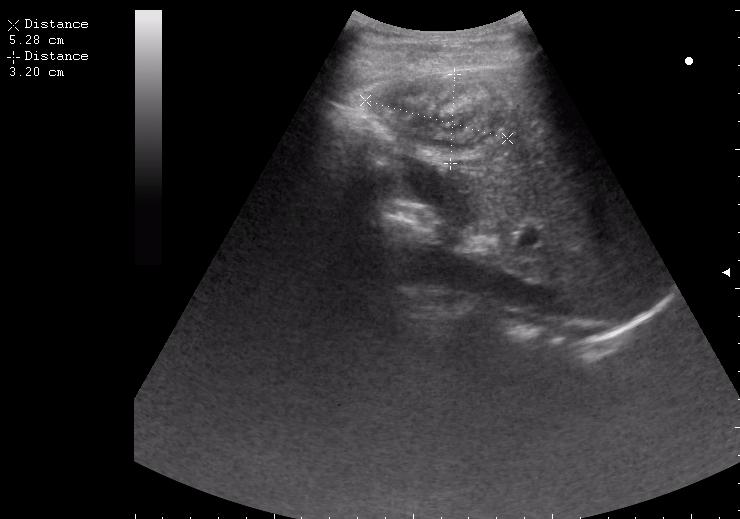

17-летняя девушка с множественными поражениями печени

абсцесс передней брюшной стенки (через 2 недели п.о.)